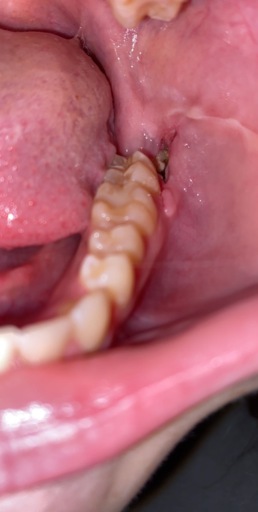

Hi, I have a frenulum on the right side of my mouth. It connects to my gums about 1cm behind the upper and lower back molars. It has become tight and painful. Have you ever seen anything like this? Is it safe to have it cut? I will attempt to add a photo. Thank you, H. Jay Graber

A frenum or frenulum is a small fold of tissue that restricts and secures the motion of a mobile organ.  I have not heard of a frenulum in the back of the mouth. It would be best to bring this to the attention of your dentist, especially because it is causing discomfort.  I did not see a picture attached to your question, however I am wondering if it is part of your cheek or possibly an impacted tooth that may be causing this discomfort.  Use warm salt water rinses several times a day to soothe the tissues until you have a proper exam and diagnosis.

A frenulum or frenum is a small fold of tissue that restricts or secures the motion of a mobile organ.  I have not seen a fold of tissue (unless sutured) that connects distal to the molars.  There is a frenum that connects your tongue to the floor of your mouth as well as one that attaches your lips to your jaws.  Since you are experiencing pain, it is important for you to see your dentist immediately to be sure you do not have an infection or a tooth that is creating swelling in the area.